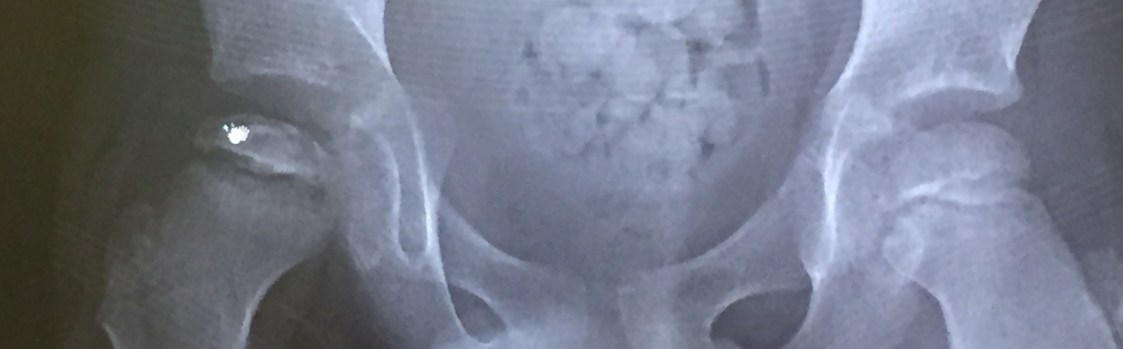

Nov scan1

X-ray image